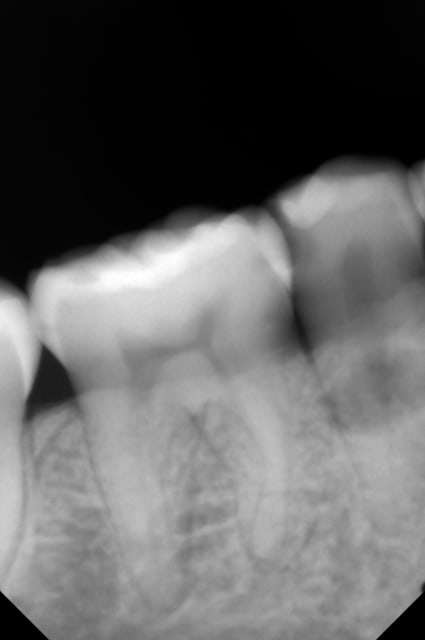

Une patiente 25 ans me décrit des douleurs relativement intenses au froid sur la 45. Je fais une rétro, je visualise la carie et une image radioclaire en regard de la 45.

Sinon pour les caries il y a aussi 45m amélaire idem 44d+ 46m dentinaire à priori et idem en d mais doute sur amélaire.

les douleurs au froid peuvent être liées au syndrome septum car on voit bien une atteinte radio à ce niveau.

l'image radio-claire peut être fortuite dans la mesure où elle ne semble pas du tout liée à 45 d'après tes différents clichés cette lésion serait davantage sur le versant lingual.